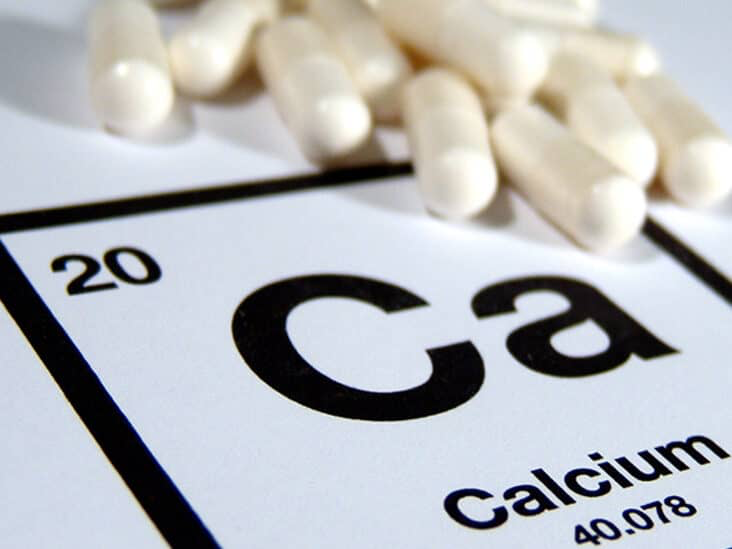

بهترین دکتر هیپرکلسمی مشهد + لیست 10 تایی